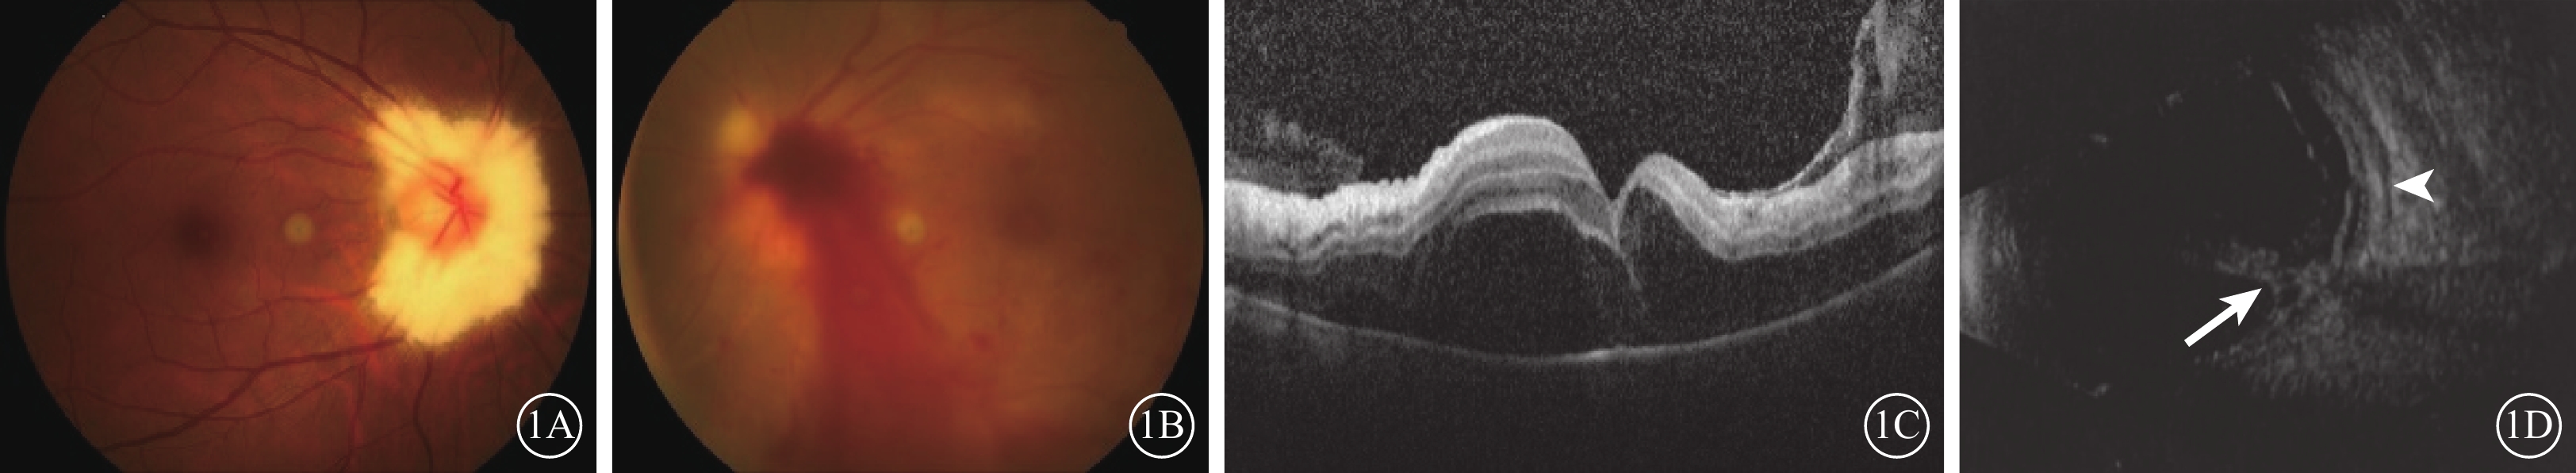

患者女,40歲。因左眼突然視物模糊伴眼紅、眼球轉動痛7 d,于2020年1月6日到北京同仁醫院眼科中心就診。患者既往身體健康,無眼部疾病史;否認發熱、頭痛、咳嗽、胸痛、胃痛、潰瘍、皮膚病損及關節病;3周前接受宮內節育器植入手術。眼科檢查:右眼視力1.0;左眼視力0.1,未進行矯正。右眼、左眼眼壓分別為13、19 mm Hg(1 mm Hg=0.133 kPa)。右眼眼前節檢查未見異常;左眼結膜充血,角膜透明,可見羊脂狀角膜后沉著物(+),前房細胞(++),玻璃體混濁。眼底檢查,右眼有髓神經纖維(圖1A);左眼視盤致密玻璃體積血,周圍多個視網膜下白色病灶及視網膜動脈鞘(圖1B),無周邊視網膜局灶性病灶。光相干斷層掃描(OCT)檢查,左眼視網膜下液(圖1C)。眼B型超聲檢查,左眼玻璃體混濁,視網膜、脈絡膜水腫,鞏膜增厚(圖1D)。眼眶磁共振成像(MRI)檢查,左側視神經形態扭曲,稍增粗,視神經鞘稍增厚,DWI呈稍強信號。右眼OCT、眼B型超聲及眼眶MRI檢查均未見異常。顱腦MRI檢查無異常。患者血清學檢查示單純皰疹病毒(HSV)1- IgG、巨細胞病毒(CMV)-IgG、風疹病毒-IgG陽性。左眼房水聚合酶鏈反應檢測示HSV-1陽性(滴度:2.51×104/ml),帶狀皰疹病毒、CMV、Epstein-Barr病毒、內參基因26SrRNA、革蘭氏陰性菌脂多糖、真菌(1-3)-β-D葡聚糖陰性。眼房水白細胞介素-6水平38 696.2 pg/ml(參考值范圍1.0~50.0 pg/ml)。血常規及生化常規檢測結果正常。人類免疫缺陷病毒、梅毒、肝炎檢測結果陰性。診斷:左眼急性視網膜壞死(ARN)、左眼后鞏膜炎。